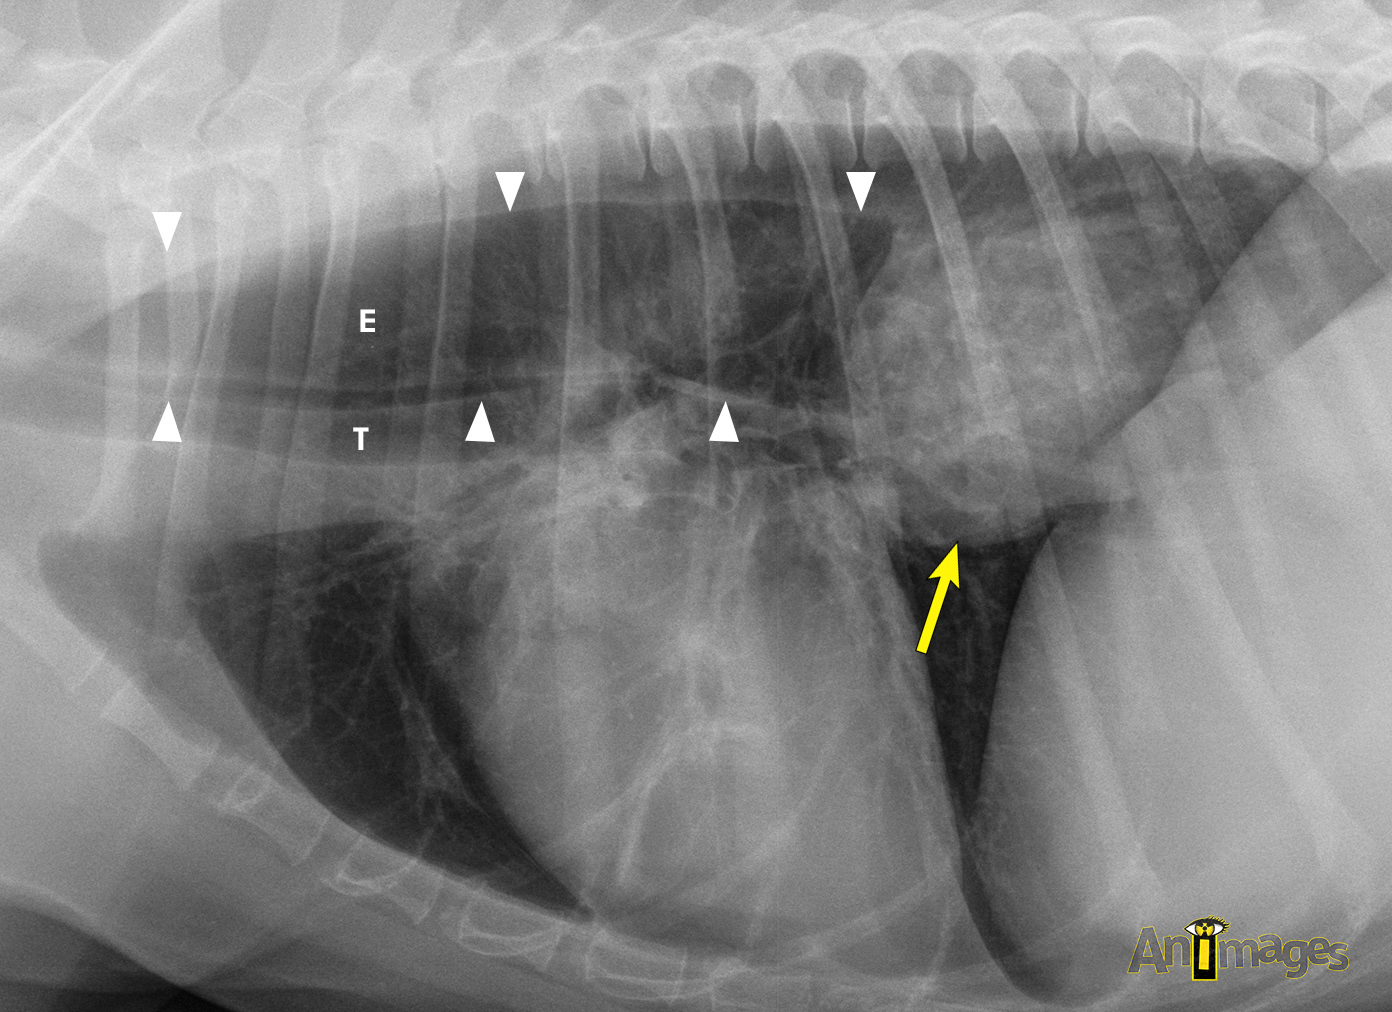

Latérale droite